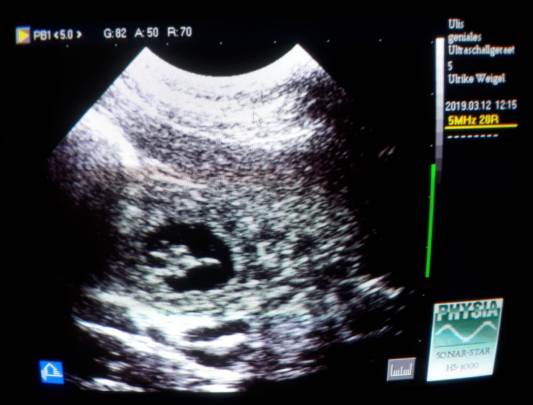

Denn auf dem Ultraschall sind selten alle zu sehen.

Welche Freude beim Ultraschall im Wohnzimmer (meist schauen viele mit zu..;)

wenn die schwarzen Fruchthüllen mit den kleinen "Gummibärchen" drin zu sehen sind!!!!

Meine Kinder haben mir vor Jahren ein kleines Ultraschallgerät geschenkt,

welches für diesen Zweck hervorragend geeignet ist!

Jedesmal ist es für mich eine riesige Freude :)